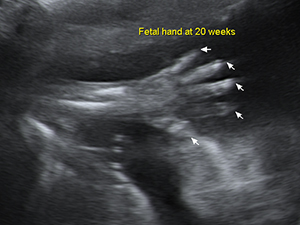

The fetal hand at 20 weeks Gender - Male